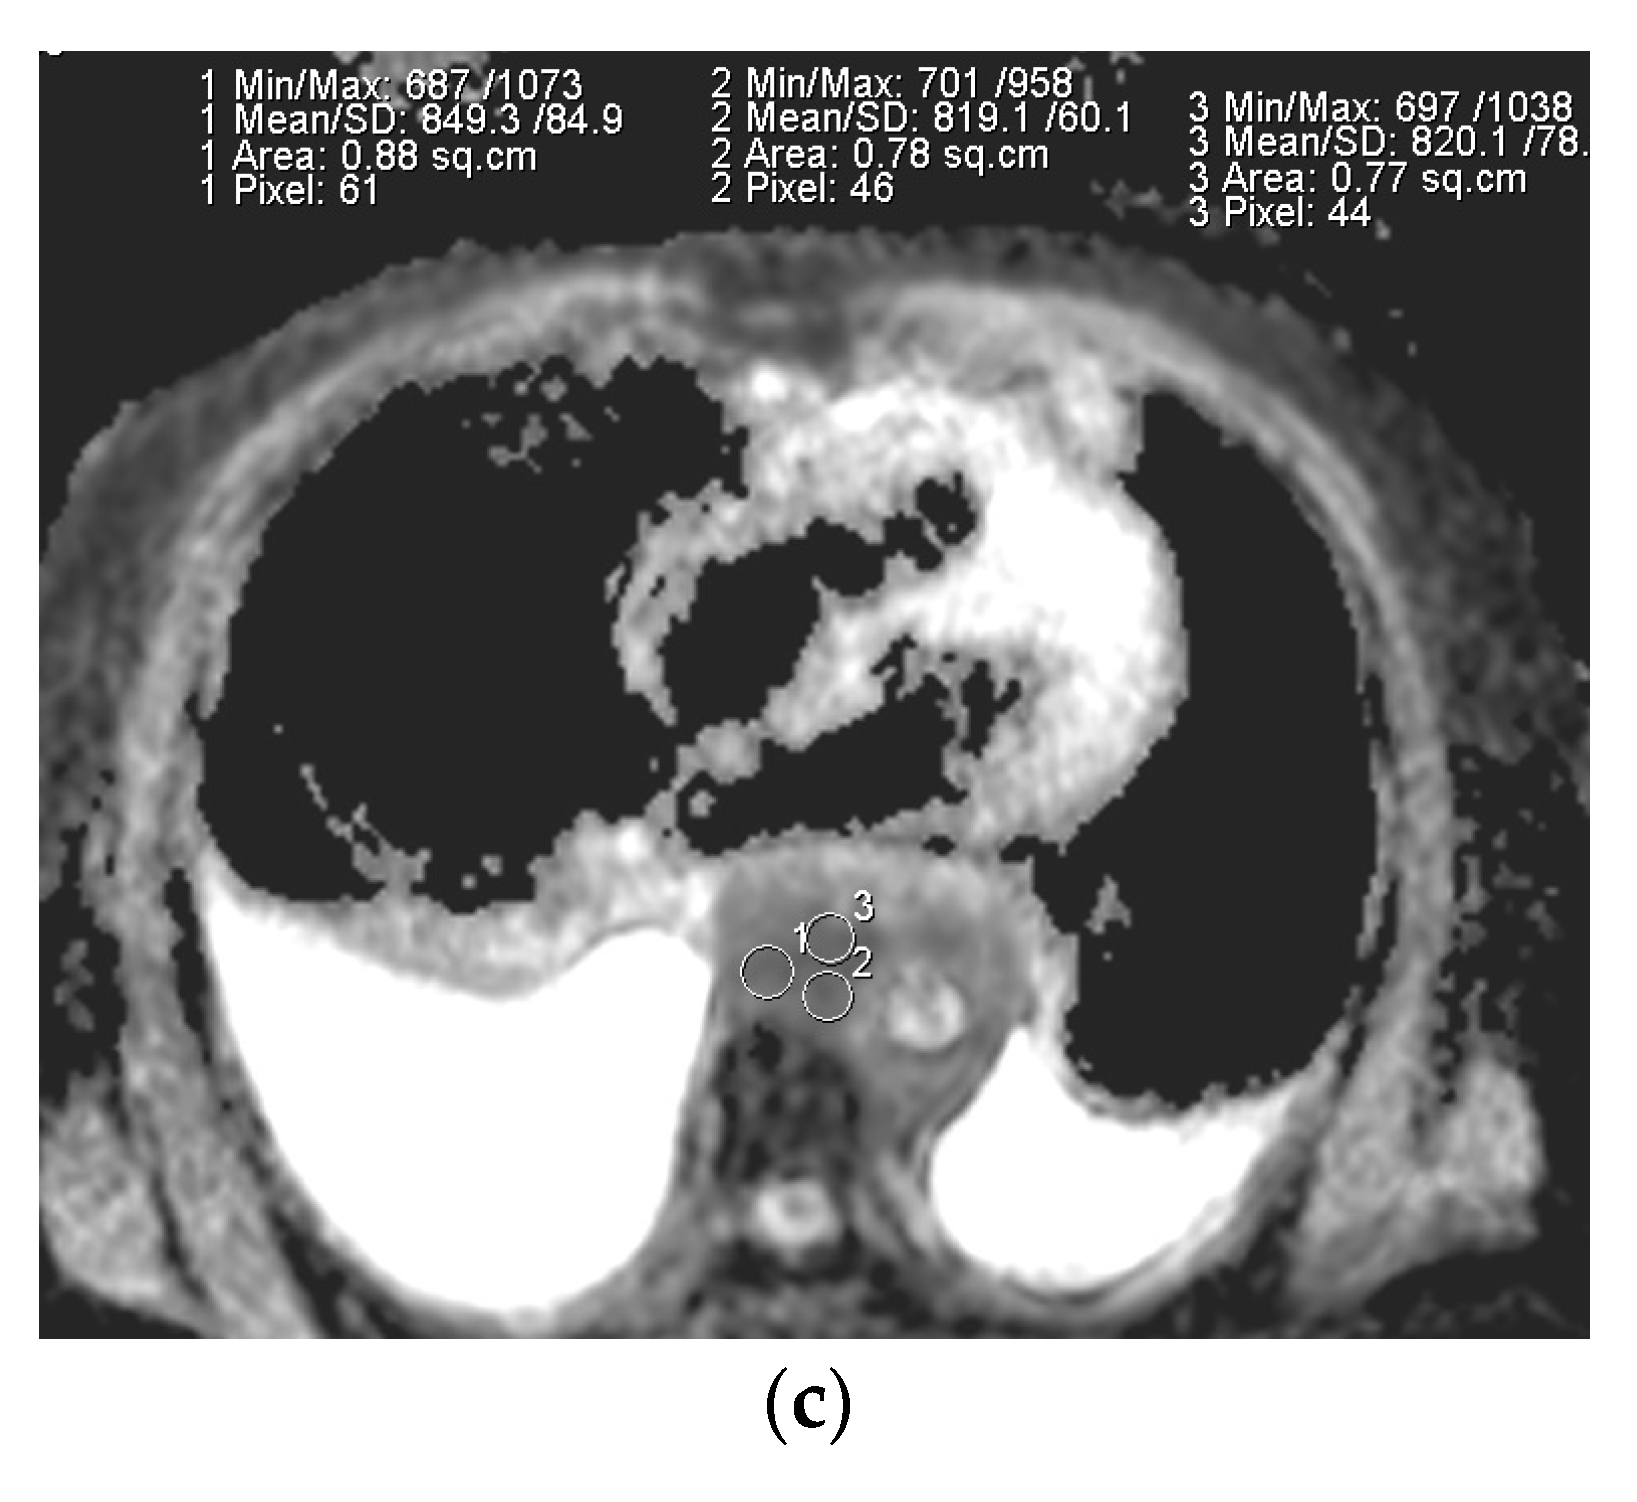

Figure 4.

Box and whisker plot of the ADC mean value of the benign versus malignant mediastinal lymph nodes.°-denotes the maximum ADC mean value in the malignant group.